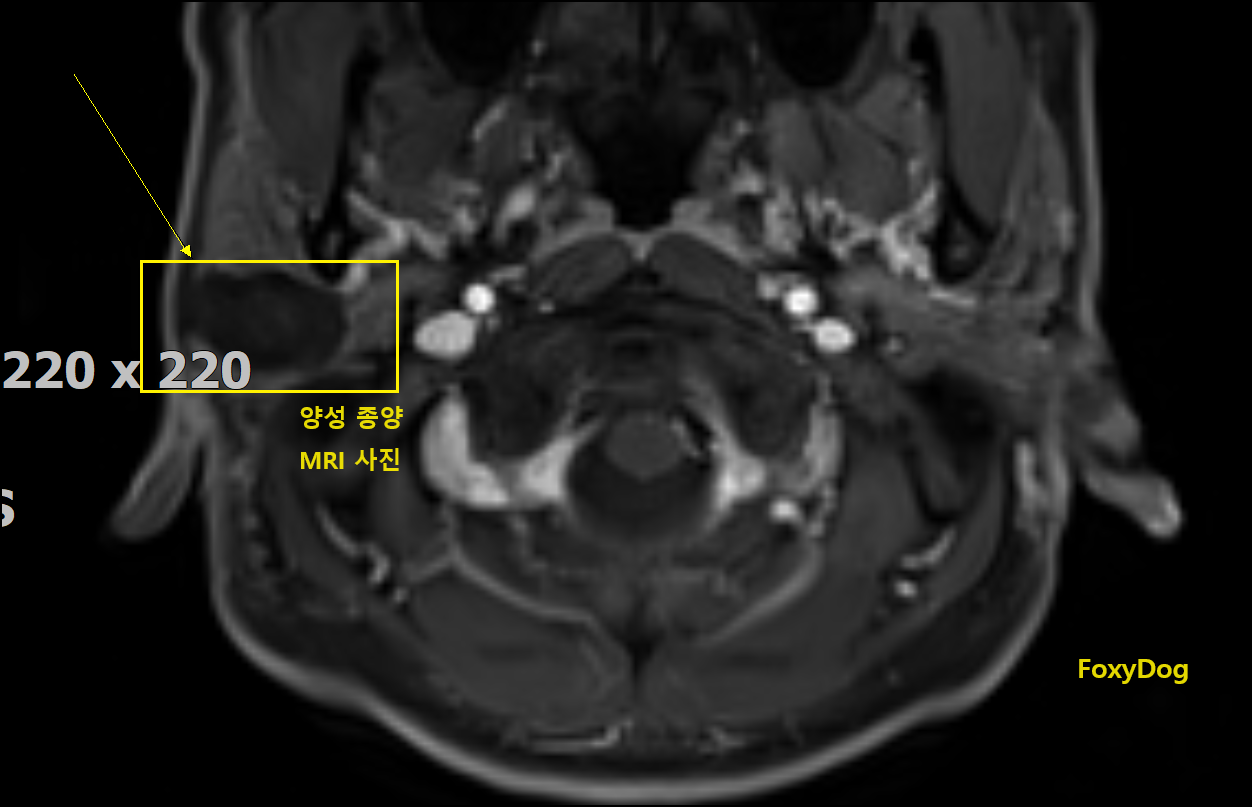

드디어 최종 검사 결과를 확인하였는데, 역시 겉으로 보는 것보다 MRI 영상에서 보인 양성 종양이 가로 세로 약 3x3cm 정도의 타원형태로 침샘부위에 자라고 있는 게 확인이 되었다. 다행히 세포 조직 검사에서는 악성은 아니고 일반적인 양성 종양으로 (임시) 판별되었다. 그냥 놔두어도 큰 문제는 없을 수 있지만 그래도 대부분 주치의 선생님은 수술을 하시는 것을 권하였다. 확률은 매우 낮지만 또 이런 종양이 모종의 이유로 갑자기 악성 종양(암)으로 변질될 확률도 있다는 것이다. 필자의 경우는 변수가 생겼는데 종양이 얼굴 근육 섬유에 둘러싸여 안쪽까지 깊게 들어가 있어서 실제 수술로 열어봐야 상황을 알 수 있다고 하셨다.